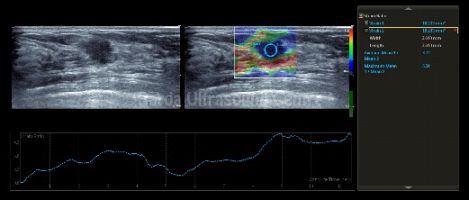

Dedicated 4D curvilinear and transvaginal probes help in more accurate diagnosis in fetal abnormalities and uterine anomalies. Micro-vascular flow imaging picks up smallest of flow on doppler; specially useful in endometrial doppler, torsion, soft tissue masses, arthritis, etc.